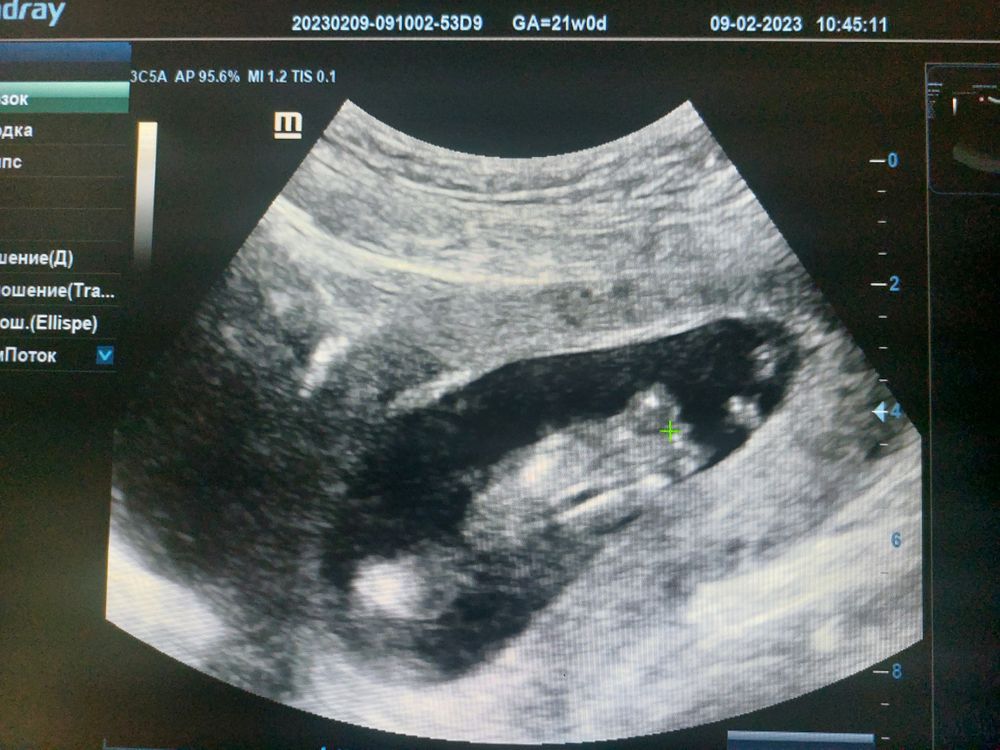

Ничего не скажу, на таком сроке смотрят пол по бугорку. Нужно фото малыша сбоку. Тут не видно.

Enotik Lesnoy , то место где + это где бугорок когда она делала узи очень был похож на мальчика

Саяна , снизу, на этом сроке все похожи на мальчика.

Саяна, ок, объясню иначе: ещё не сформированы наружные половые органы у плода на этом сроке. В 16 недель сходите или кровь сдайте.

Саяна , вам ниже написали очень верно ) на этом сроке невозможно с такого ракурса определить пол дождитесь недель 15